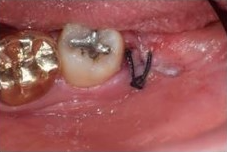

✅3일차 / 4일차

4일차에 실밥이 제거된 모습입니다.

보통은 발치후 일주일 정도 후

내원하여 실밥제거와 함께

회복상태를 체크합니다.

4~5일차가 되면

봉합실이 느슨하다고 느껴질 수 있는데

이는 잇몸이 어느정도 아물고

안정화가 되어 그런것입니다.

모르는 사이 풀렸다해도

큰 걱정은 하지 안하도 되며

약속한 날짜에 치과에 방문하여

실밥을 제거하고 소독을 받으면 됩니다.

실밥제거시 잇몸을 스치는 느낌이 있지만

별다른 통증은 거의 없는 수준입니다.

물론 이보다 빠른날 혹은 봉합당일 풀렸다면

치과에 문의하여

적절한 조치를 받으셔야 합니다.

3일차 / 4일차